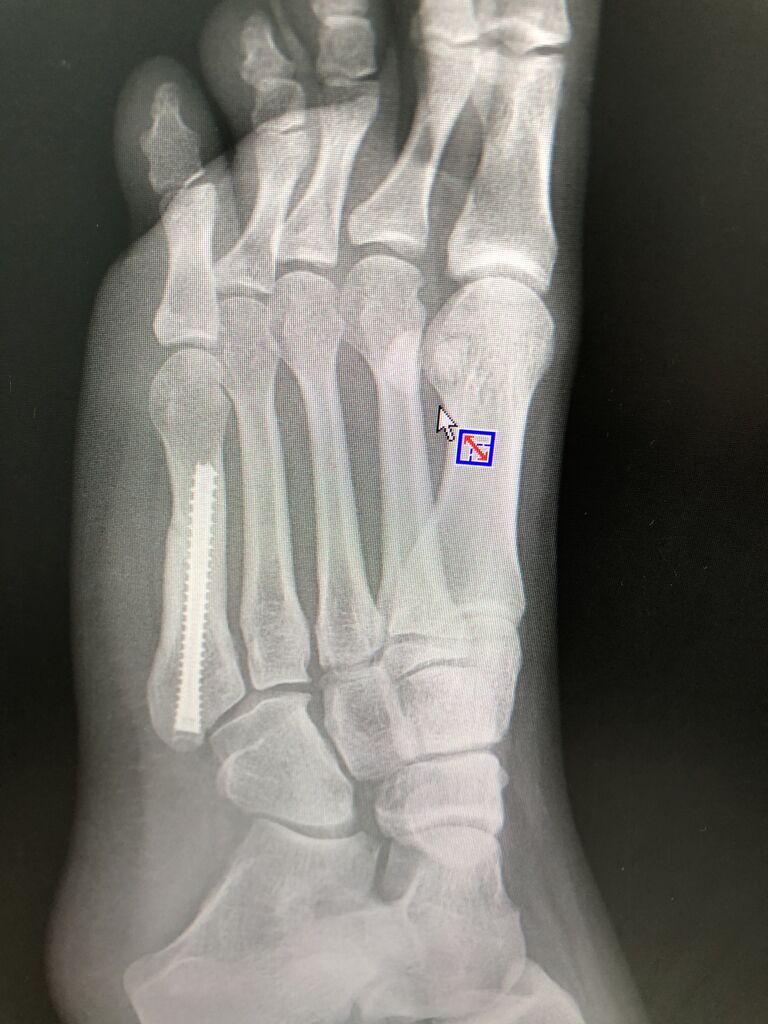

2020年07月09日 ダンス アスリート骨折 他院を転々しても良くならず ダンストップアスリートが相談です 非常につきにくい所の骨折です プロは早めからスクリュー固定した方が早期 復帰できるのてす . カテゴリなしの他の記事 < 前の記事次の記事 >